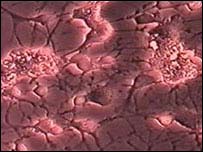

Neurônios

O cérebro continua a produzir neurônios depois de adulto